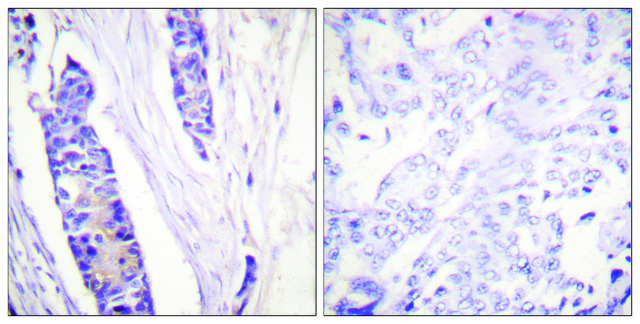

ELISA: 1:5000

immunohistochemistry: 1:50-1:100

western blot: 1:500-1:1000